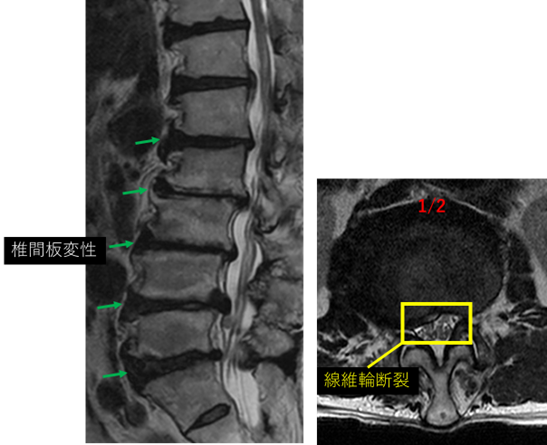

画像及び所見について

L1/2: 椎間板変性、膨隆、左椎間孔狭窄、繊維輪断裂

L2/3: 椎間板変性、膨隆、両椎間孔狭窄、終板変性

L3/4: 椎間板変性、膨隆、両椎間孔狭窄、終板変性

L4/5: 椎間板変性、膨隆、右椎間孔狭窄、終板変性

L5/S: 椎間板変性、膨隆、両椎間孔狭窄、終板変性

以上の事が画像上認められます。

L1/2、2/3、3/4、4/5、5/S に

椎間板変性、膨隆、左椎間孔狭窄、繊維輪断裂、終板変性 を認め、主症状の原因の可能性が高い。